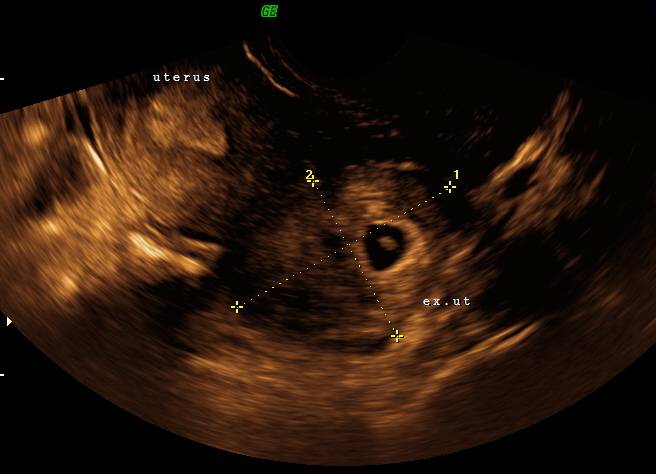

Ultralydsskanning som viser en intrauterin graviditet. Fosterets længde (crown rump length - CRL) er 4 mm (markeret med krydser).